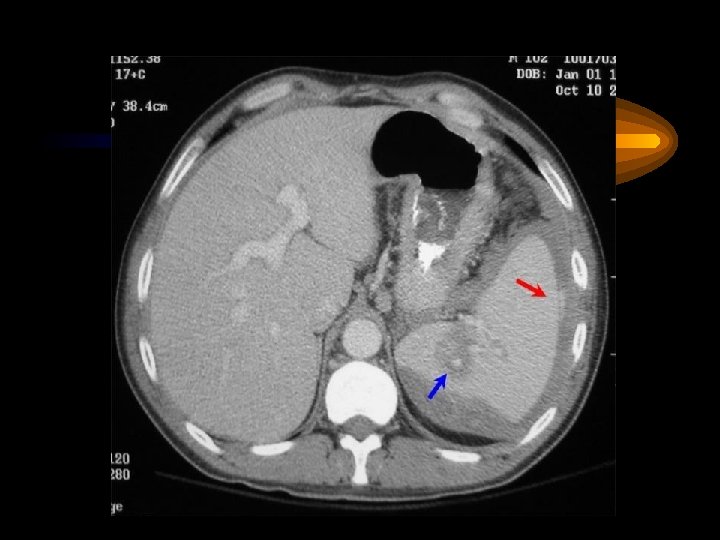

Pankreas Akut pankreatitis Karın ağrısı, bulantı-kusma, şok Nedenler Safra kesesi-yolları taşları Alkol Virüsler Hiperlipidemi, İatrojenik Tanı Serum amilazı yükselir Abd. CT ve US komplikasyonlar pseudokist, flegmon abse